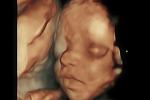

Ohio bill would introduce fetal development into school curriculum Watch

A recently introduced bill in Ohio would add scientific information about the development of the unborn child to the state's public and ... continue reading